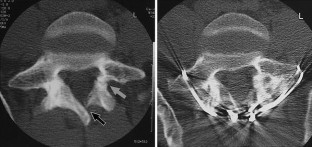

Fig. 1

Fig. 2

Fig. 3

Fig. 4